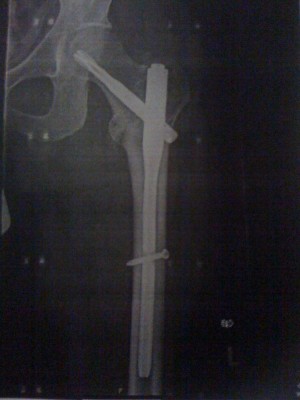

Bloß nicht ungeduldig werden! Bei unserem Luis ist es schlimmer!!!

Knochen heilen mit Schrauben und Nägeln schneller! :aaah: :adas

Foto.jpg

Foto.jpg [ 128.09 KiB | 2141-mal betrachtet ]

radunfall? sieht übel aus...

Blitz-Eis am 22.12.09!